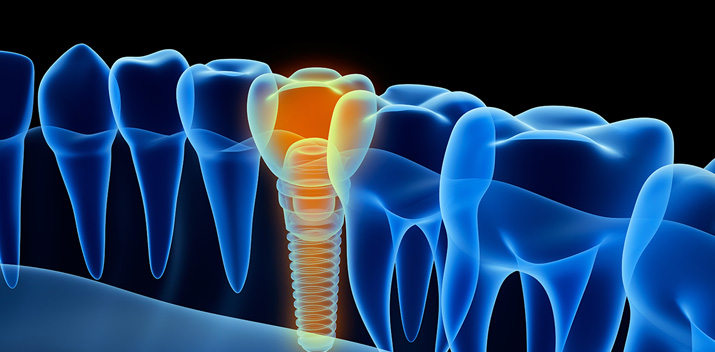

For cutting edge treatments such as implants it provides a wealth of information to allow specialists to make faster and more informed decisions about the treatments they can offer.

• Instrumental in delivering the information needed for dental implants